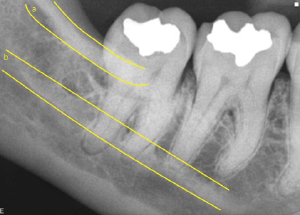

76. What is B showing?

Internal oblique ridge is the bony protuberance located on the lingual surface of mandible extending diagonally downward from the ramus and ending anteriorly near the apices of the premolars. Its function is to serve as an attachment site for the mylohyoid muscle of the floor of the mouth.

77. What is A showing?